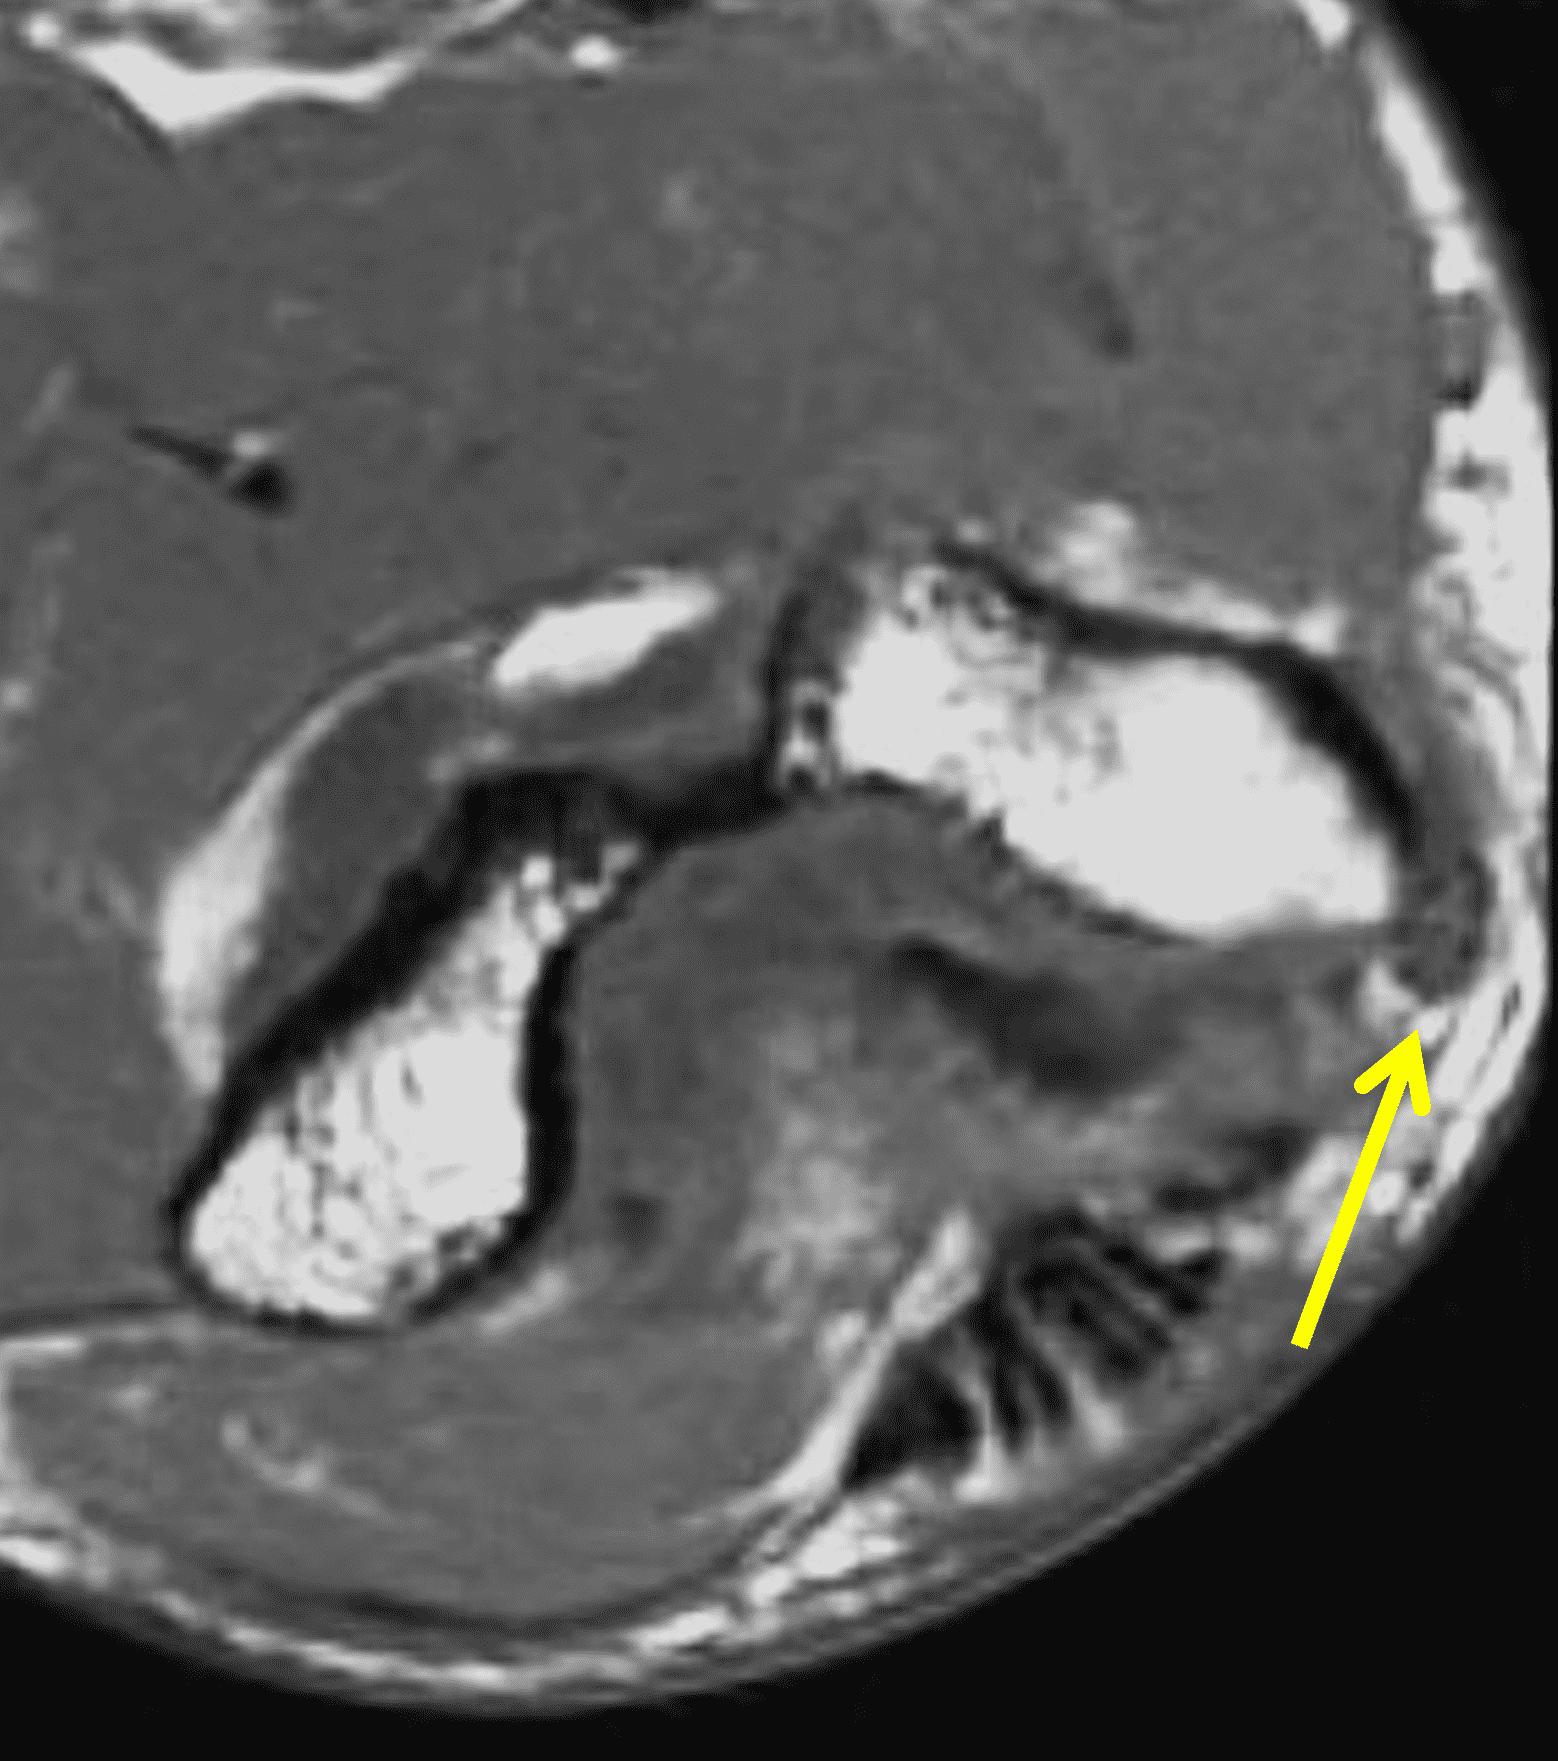

Figure 2: At the level of the cubital tunnel (2A and 2C), identifiable by the thin cubital tunnel retinaculum (yellow arrow), the ulnar nerve (red arrow) is focally enlarged and hyperintense compared to the nerve more distally (2B and 2D), where it lies between the two heads of the flexor carpi ulnaris muscle (asterisks). No soft tissue mass is present.